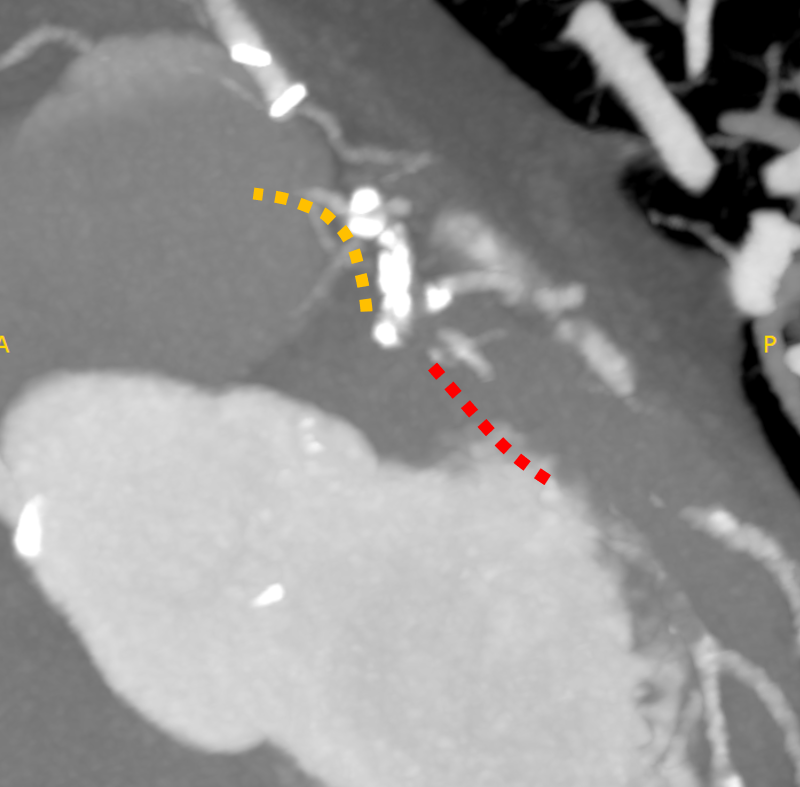

The left internal thoracic artery–left anterior descending artery (LAD) graft was completely occluded, and the native left coronary artery (LCA) was also occluded at the ostium of the left main trunk (LMT). The right coronary artery demonstrated no significant stenosis. From a right ventricular branch, non-interventional epicardial channels opacified the separated LAD and left circumflex artery. The occlusion length from the ostium of the long LMT to the bifurcation, was approximately 15 mm.

First, percutaneous coronary intervention (PCI) was performed toward the left anterior descending artery (LAD). The initial antegrade wire deviated from the true lumen; therefore, parallel wire technique was employed to achieve successful crossing. To avoid jailing the left circumflex artery (LCX) ostium, the stent was deployed precisely at the LAD ostium, and the left main trunk (LMT) was dilated using a 4.0-mm cutting balloon. One month later, intervention toward the LCX was undertaken. Intravascular ultrasound (IVUS) performed from the LAD confirmed achronic total occlusion (CTO) entry with a markedly thick plaque covering the LCX ostium. Although the lesion was accurately marked, penetration with a high-penetration guidewire was unsuccessful. Even with the balloon screen technique using a CP 8-20, wire penetration remained unsuccessful. Therefore, plaque debulking was selected to expose the CTO entry. Directional coronary atherectomy (DCA) was performed, and follow-up IVUS demonstrated significant plaquethinning compared with baseline. Subsequently, the CP 8-20 wire advanced smoothly, enabling successful wire crossing. The procedure was completed usinga mini-crush stenting strategy.

Aorto-ostial CTO of the LMT is extremely rare, accounting for approximately 0.1% of all CTOs. In this case, the lesion was particularly unique due to its unprotected LMT, absence of retrogradeoption, and completely separated distal bifurcation. In a bifurcation with separated branches, successful wire passage into one branch inevitably resultsin ¡°short-cut¡± the entry of the other branch. In this case, cutting angioplasty could not modify the cap; therefore, directional coronary atherectomy (DCA) was employed. Although DCA is currently approved only in Japan, the essential concept is targeted plaque modification at the entry, which may also be achieved with other atherectomy modalities.